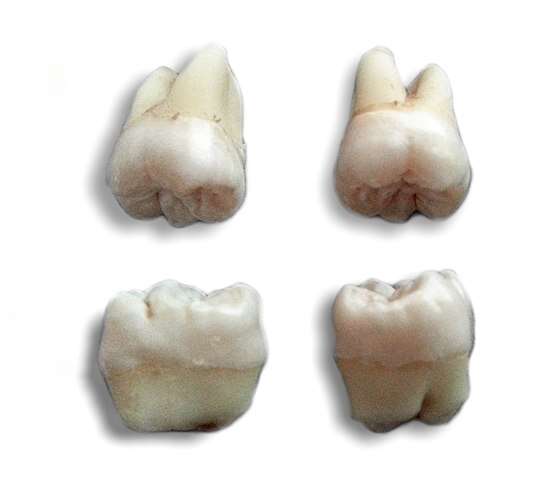

Dorosły człowiek powinien mieć 32 zęby – 12 trzonowców, 8 przedtrzonowców, 4 kłów i 8 siekaczy. Ich zadania są całkiem inne – siekacze służą do odgryzania kęsów, kły do chwytania, a przedtrzonowce i trzonowców do miażdżenia i rozcierania pokarmu. To dlatego, że poszczególne typy zębów różnią się od siebie anatomicznie – wystarczy choćby spojrzeć na ich kształt.

Problem polega na tym, że w szczękach większości ludzi mieści się tylko 30 w pełni wykształconych zębów (taka fizjologia). Brakuje w nich miejsca dla ostatnich zębów trzonowych, czyli tzw. ósemek. Są one nazywane zębami mądrości, ale z IQ nie mają nic wspólnego – po prostu wyrzynają się jako ostatnie. Zwykle między 17. a 21. rokiem życia, choć możliwe jest też ich pojawienie się dopiero przed czterdziestką. Zęby mądrości są jednak nam całkowicie niepotrzebne i gdy już się wykształcą, to zazwyczaj kończy się wizytą u chirurga szczękowego. W większości przypadków trzeba je bowiem usunąć.